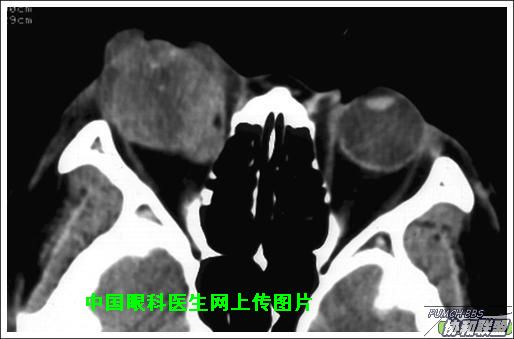

出院后半年发现右眼出现肿物,增长较快,随来京再次就诊(图1),转来我科。门诊检查发现:右眼无光感,结膜下肿物,突出睑裂。眼球突出,上移位。眶外侧可触及硬性肿物。超声(图2),CT(图3),MRI(图456)显示如图.

此主题相关图片如下:

图片点击可在新窗口打开查看